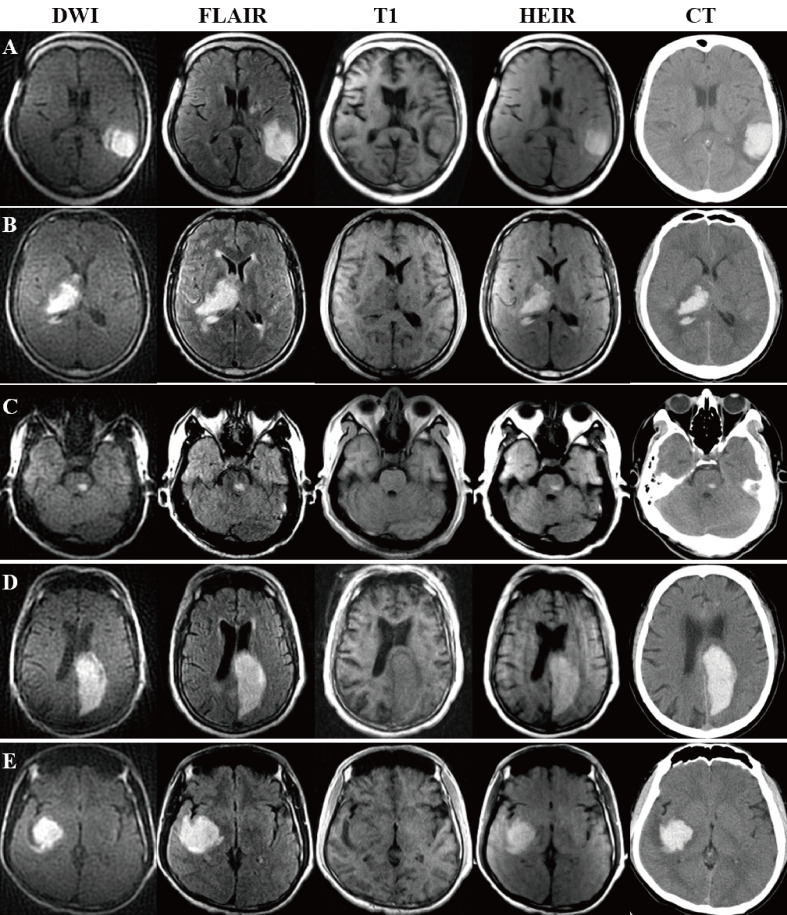

Methods: A novel HEIR sequence based on fluid-attenuated inversion recovery T1-weighted, with a scanning time of 1 min and 17 s, was developed using an ICH and AIS pig model on a 0.23-T MRI. Images of the pig model were obtained hourly for 24 hours in order to monitor value changes on T1/T2 and verify the differential diagnosis of AIS and ICH. Then, 30 patients with AIS and 30 patients with ICH with confirmed diagnoses by 3T-MRI/CT were included. Diagnostic criteria on a 0.23-T MRI for ICH was the hyperintensity signal on both the diffusion-weighted imaging (DWI) and HEIR sequence, while for AIS was the hyperintensity on DWI and isointensity on the HEIR sequence. Two blinded raters independently assessed the images obtained by the 0.23-T MRI for the presence of ICH/AIS.

Results: In the pig model, setting the inversion time to 800 ms enabled clear differentiation of ICH from brain parenchymal tissue and AIS. In real patients, a correct 0.23-T MRI diagnosis of either an AIS or ICH was made in all 60 patients within 24 hours of symptom onset (100% overall accuracy). No adverse events occurred.